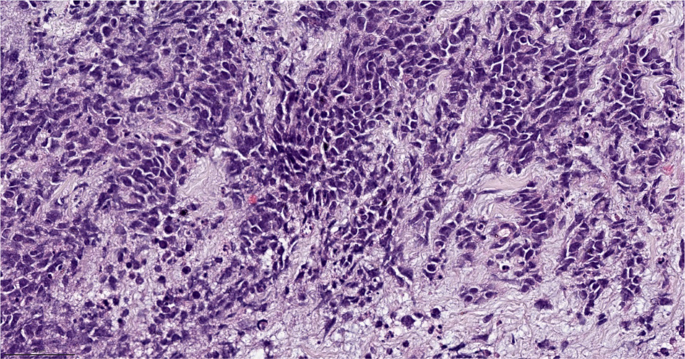

Neuroendocrine carcinoma

Neuroendocrine carcinoma of the breast is most frequently a small cell carcinoma, which represent 3–10% of extrapulmonary small cell carcinomas60,61. Neuroendocrine carcinomas of the breast tend to be poorly differentiated and hormone receptor negative. In contrast, neuroendocrine tumors of the breast are generally well differentiated and hormone receptor positive. Importantly, neuroendocrine tumors of the breast are not equivalent to carcinoid tumors at other disease sites. In the breast, the predictive and prognostic implications of neuroendocrine features are less clear, thus adjuvant treatment strategies used for invasive breast cancer no special type are also utilized for neuroendocrine breast tumors5,62. The distinct forms of neuroendocrine neoplasia of the breast, lower grade tumors versus high grade carcinomas, may develop from different pathways, similar to what has been reported for pancreatic neuroendocrine neoplasia63,64. To be identified as a pure neuroendocrine carcinoma greater than 90% neuroendocrine component is required5. When these carcinomas originate in the breast, the most common manifestation is that of an extrapulmonary small cell, though less common large cell neuroendocrine carcinomas can occur. These carcinomas are characterized by high-grade neuroendocrine morphology supported by the presence of neurosecretory granules (Fig. 9). These carcinomas are frequently characterized by TP53 and RB1 alterations63. PIK3CA mutations have been reported, though the clinical implications of this are less certain65.

High grade carcinoma exhibiting neuroendocrine morphology with hyperchromatic cells, high N:C ratio, and scant cytoplasm. Immunohistochemical stains show the tumor cells are positive for cytokeratin, neuroendocrine markers (synaptophysin, chromogranin), negative for TTF-1, with high Ki67 proliferation index (>90%) and loss of RB protein expression (not shown). Magnification 200x.